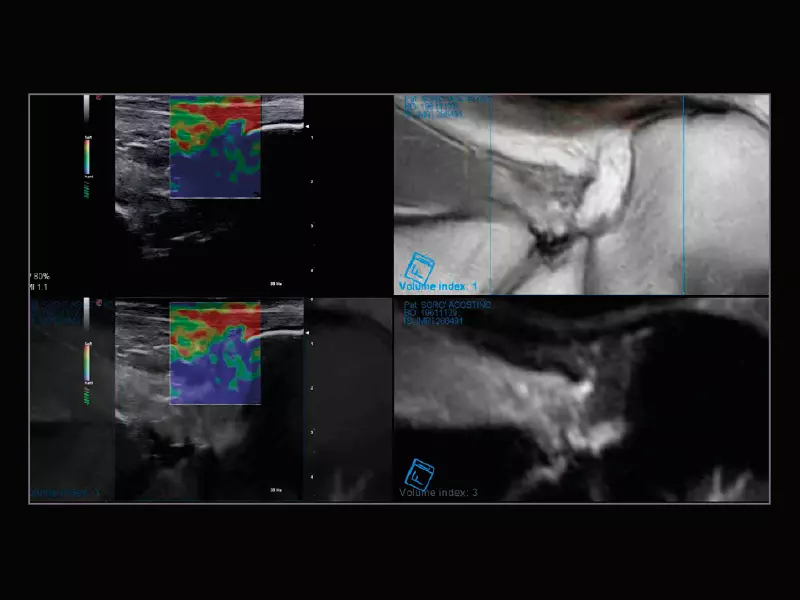

MyLab™Sigma Elite - Follow Up in real-time with a second modality

MyLab™Sigma Elite - Follow Up in real-time with a second modality